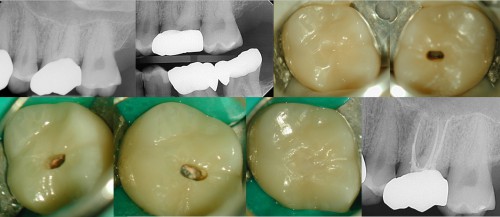

Lower Molar w/Sinus Tract, on a Recently placed Crown

Patient had a crown placed within the past six months. She developed a sinus tract […]

Max 2st Molar Tx thru New Crown

Patient had crown done a few months prior. He developed chewing pain this week. Upon […]